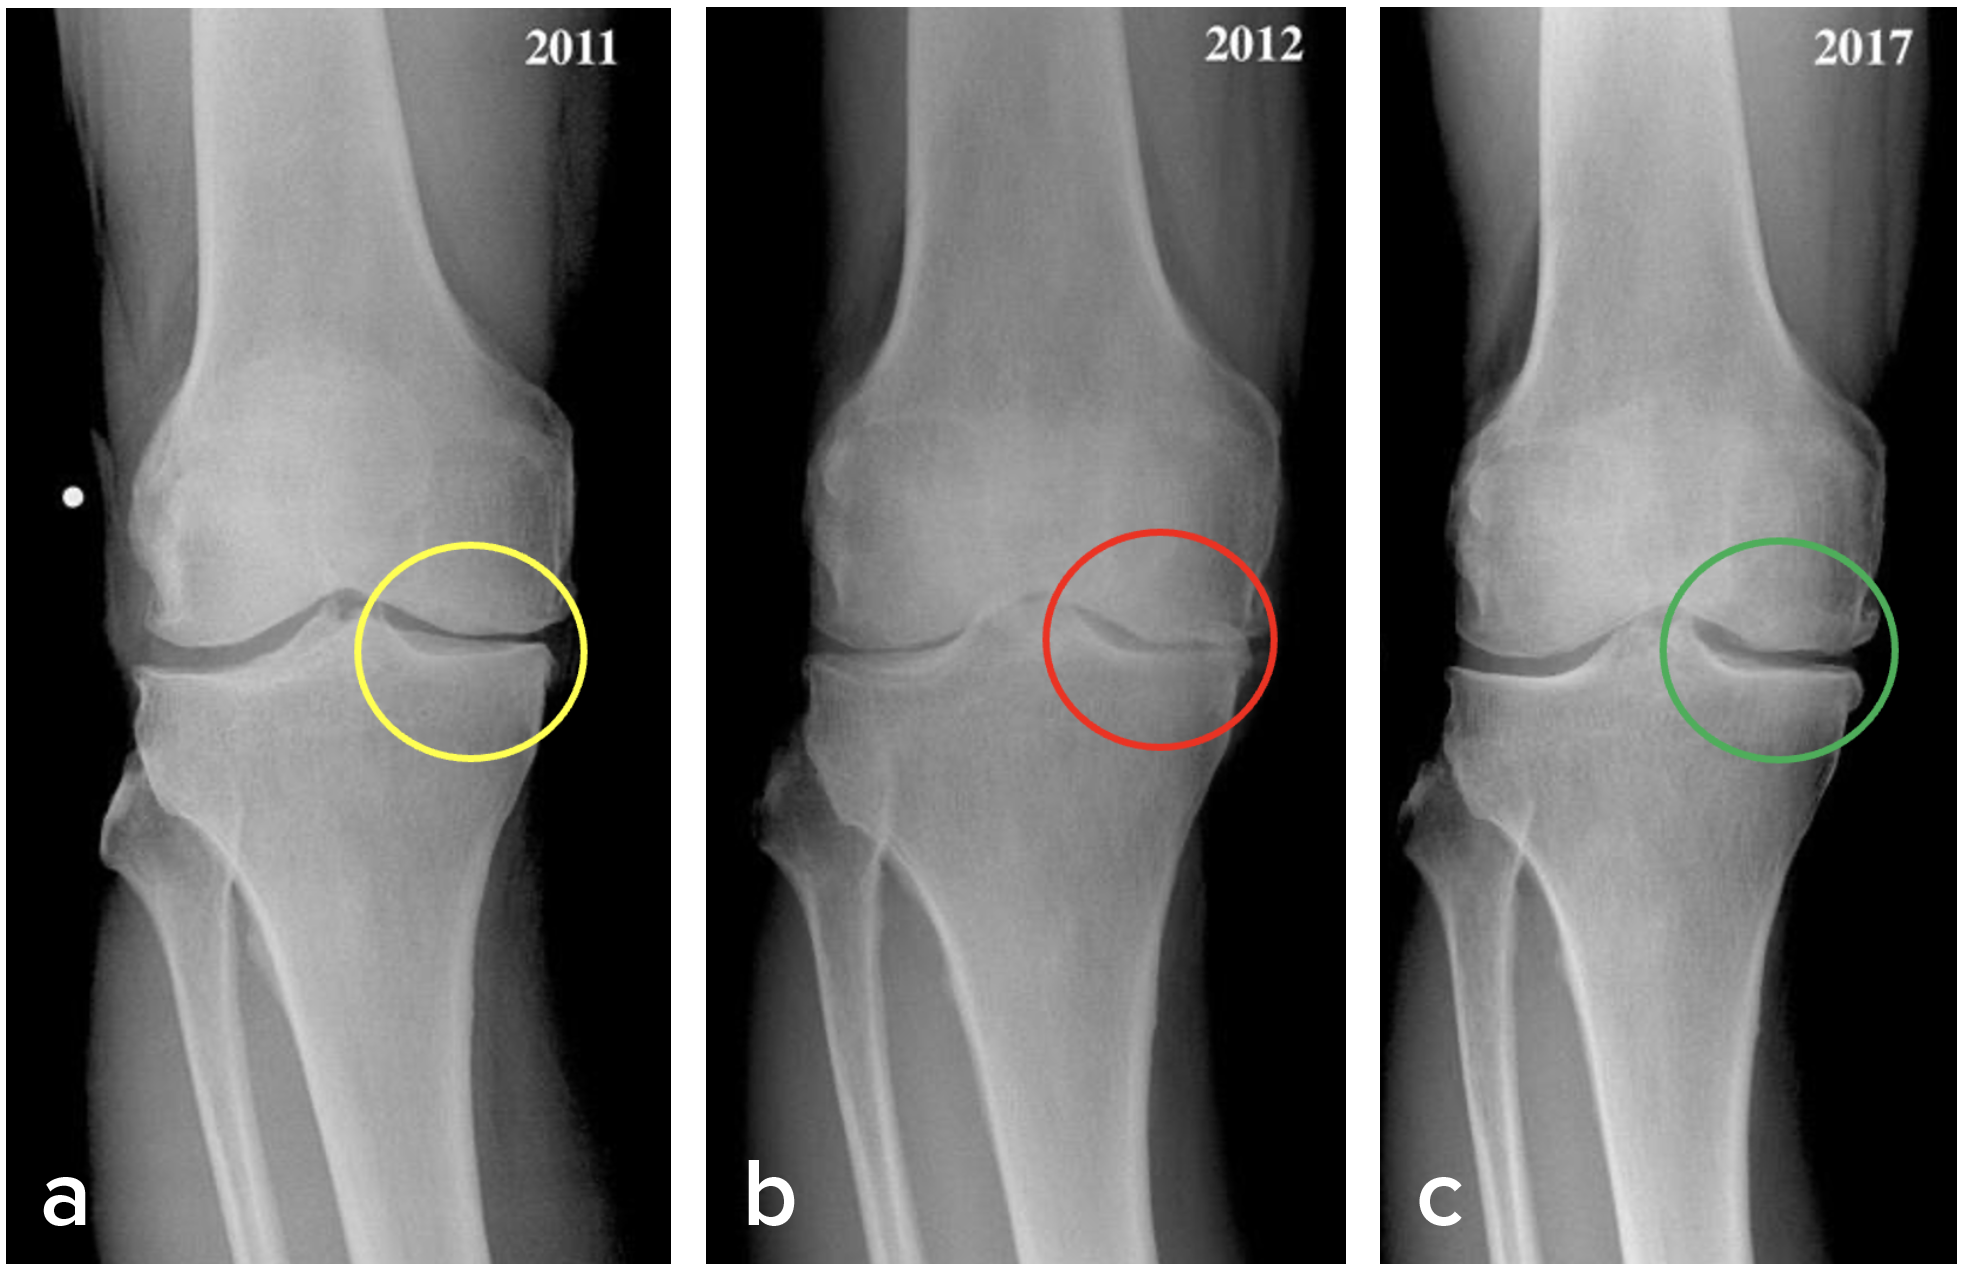

ACRFP removes the offending and abrasive medial plica and the sequalae of MAP, making the joint cavity a more hospitable space in which the damaged articular cartilage can grow back as 80% of ACRFP patients have demonstrated according to our clinical outcome studies. (4-7) Figure 3 shows an example of how ACRFP stops knee cartilage degeneration and facilitates its regeneration: a, AP standing view of a 69-year-old female patient having stage III OA over the medial compartment of her right knee; b, after one year of conservative treatment, the condition deteriorated; c. 5 years after ACRFP, X-ray images show obvious improvements in her knee.